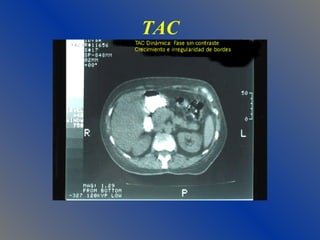

RADIOLOGIA PSA Asa Centinela (duodeno dilatado) Colon Cortado (colon transverso) Derrames pleurales (izquierdo c/amilasa) Calcificaciones (USG, TAC) USG  Mas sensibilidad para litiasis TAC Dinámica  Estudio de elección

TAC

TAC dinámica Necrosis Pancreática